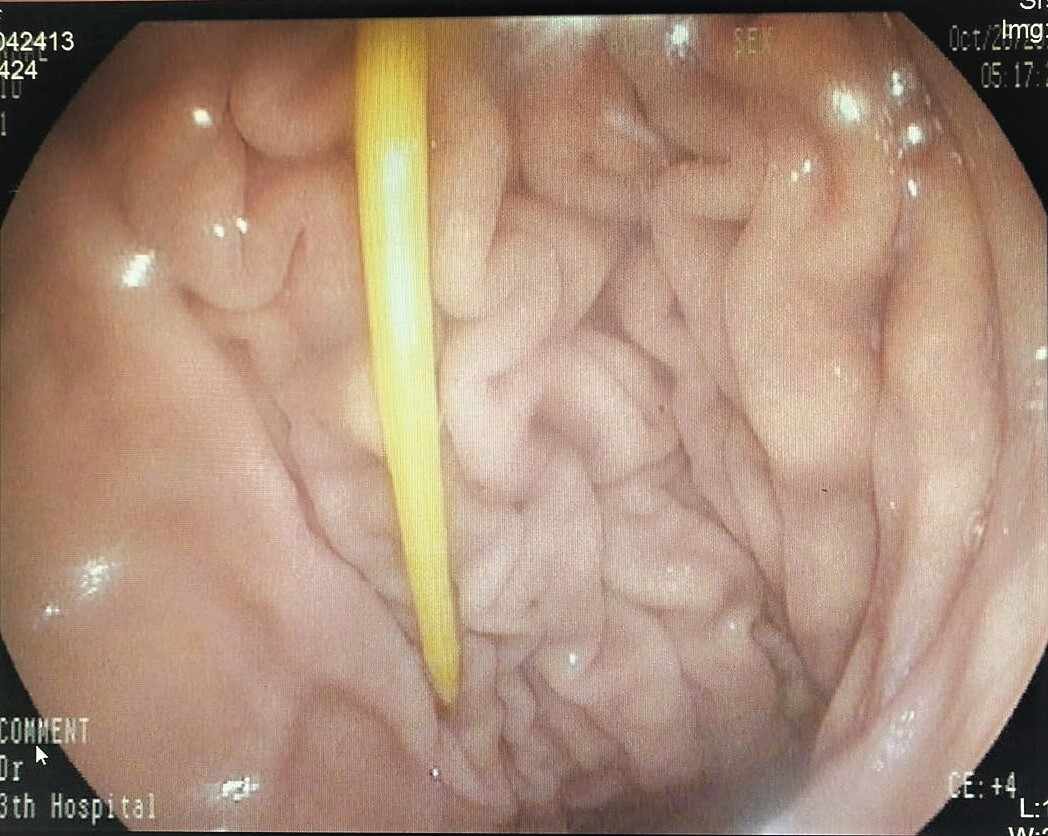

医生给张阿姨做腹部CT发现胃体部有长条状异物,考虑牙签滞留在胃内。牙签通常有6-7cm长,两头尖锐,吞服后极易造成消化道损伤甚至穿孔,严重者有可能刺穿胸腔或腹腔内大血管,随时可能有生命危险!再加上张阿姨平素有高血压、糖尿病、冠心病病史,临床操作和手术的风险较常人高出很多,病情紧急且十分棘手。发现牙签可能滞留胃内的情况后,南医三院消化内科主任岳辉带领团队立即给张阿姨进行了急诊胃镜检查,检查中果然在胃体部发现了一根牙签,所幸的是牙签尚未刺入胃壁。

在麻醉科的支持、消化内镜团队成员的配合下,岳辉主任通过胃镜无创操作,在没有引起任何附带消化道黏膜损伤的情况下,巧妙地将牙签顺利取出。手术十分顺利,术后经过1天的观察,没有任何并发症发生,老伴终于一展愁容,为张阿姨办理了出院。